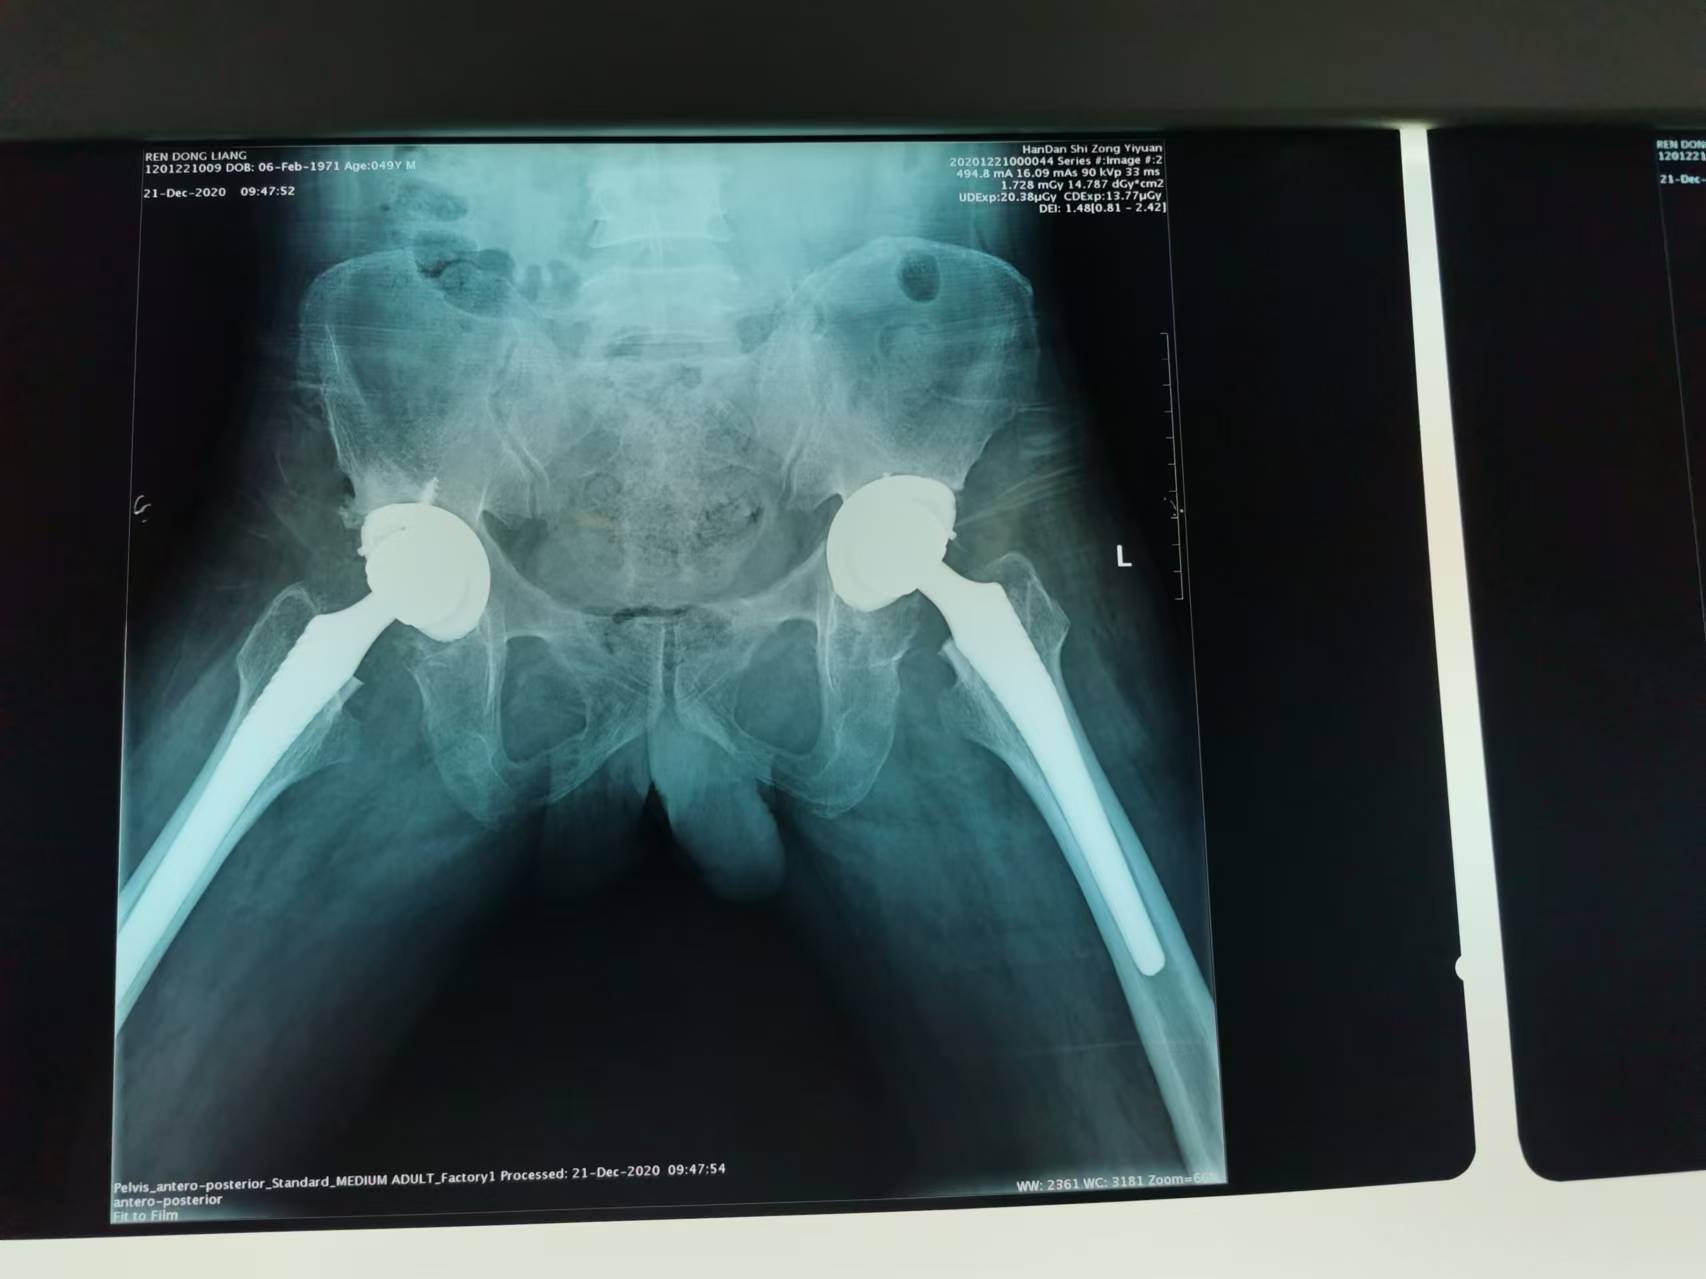

首页 > 张恒云工作室 > 影像资料 二